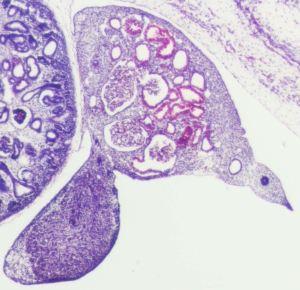

Stage 21

CfS 21

d37-39